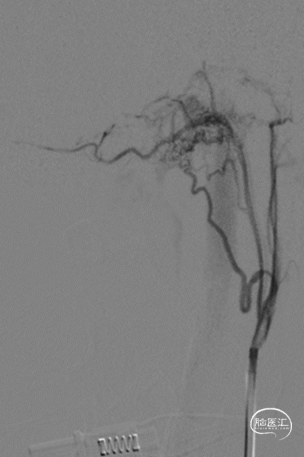

图4:DSA:LECA正位(左侧舌下神经管区硬脑膜动静脉瘘,供血动脉主要为咽升动脉神经脑膜支)

LECA:侧位(左侧舌下神经管区硬脑膜动静脉瘘,供血动脉主要为咽升动脉神经脑膜支)

LVA-正位(左侧脑膜后动脉向瘘供血)

LVA-侧位